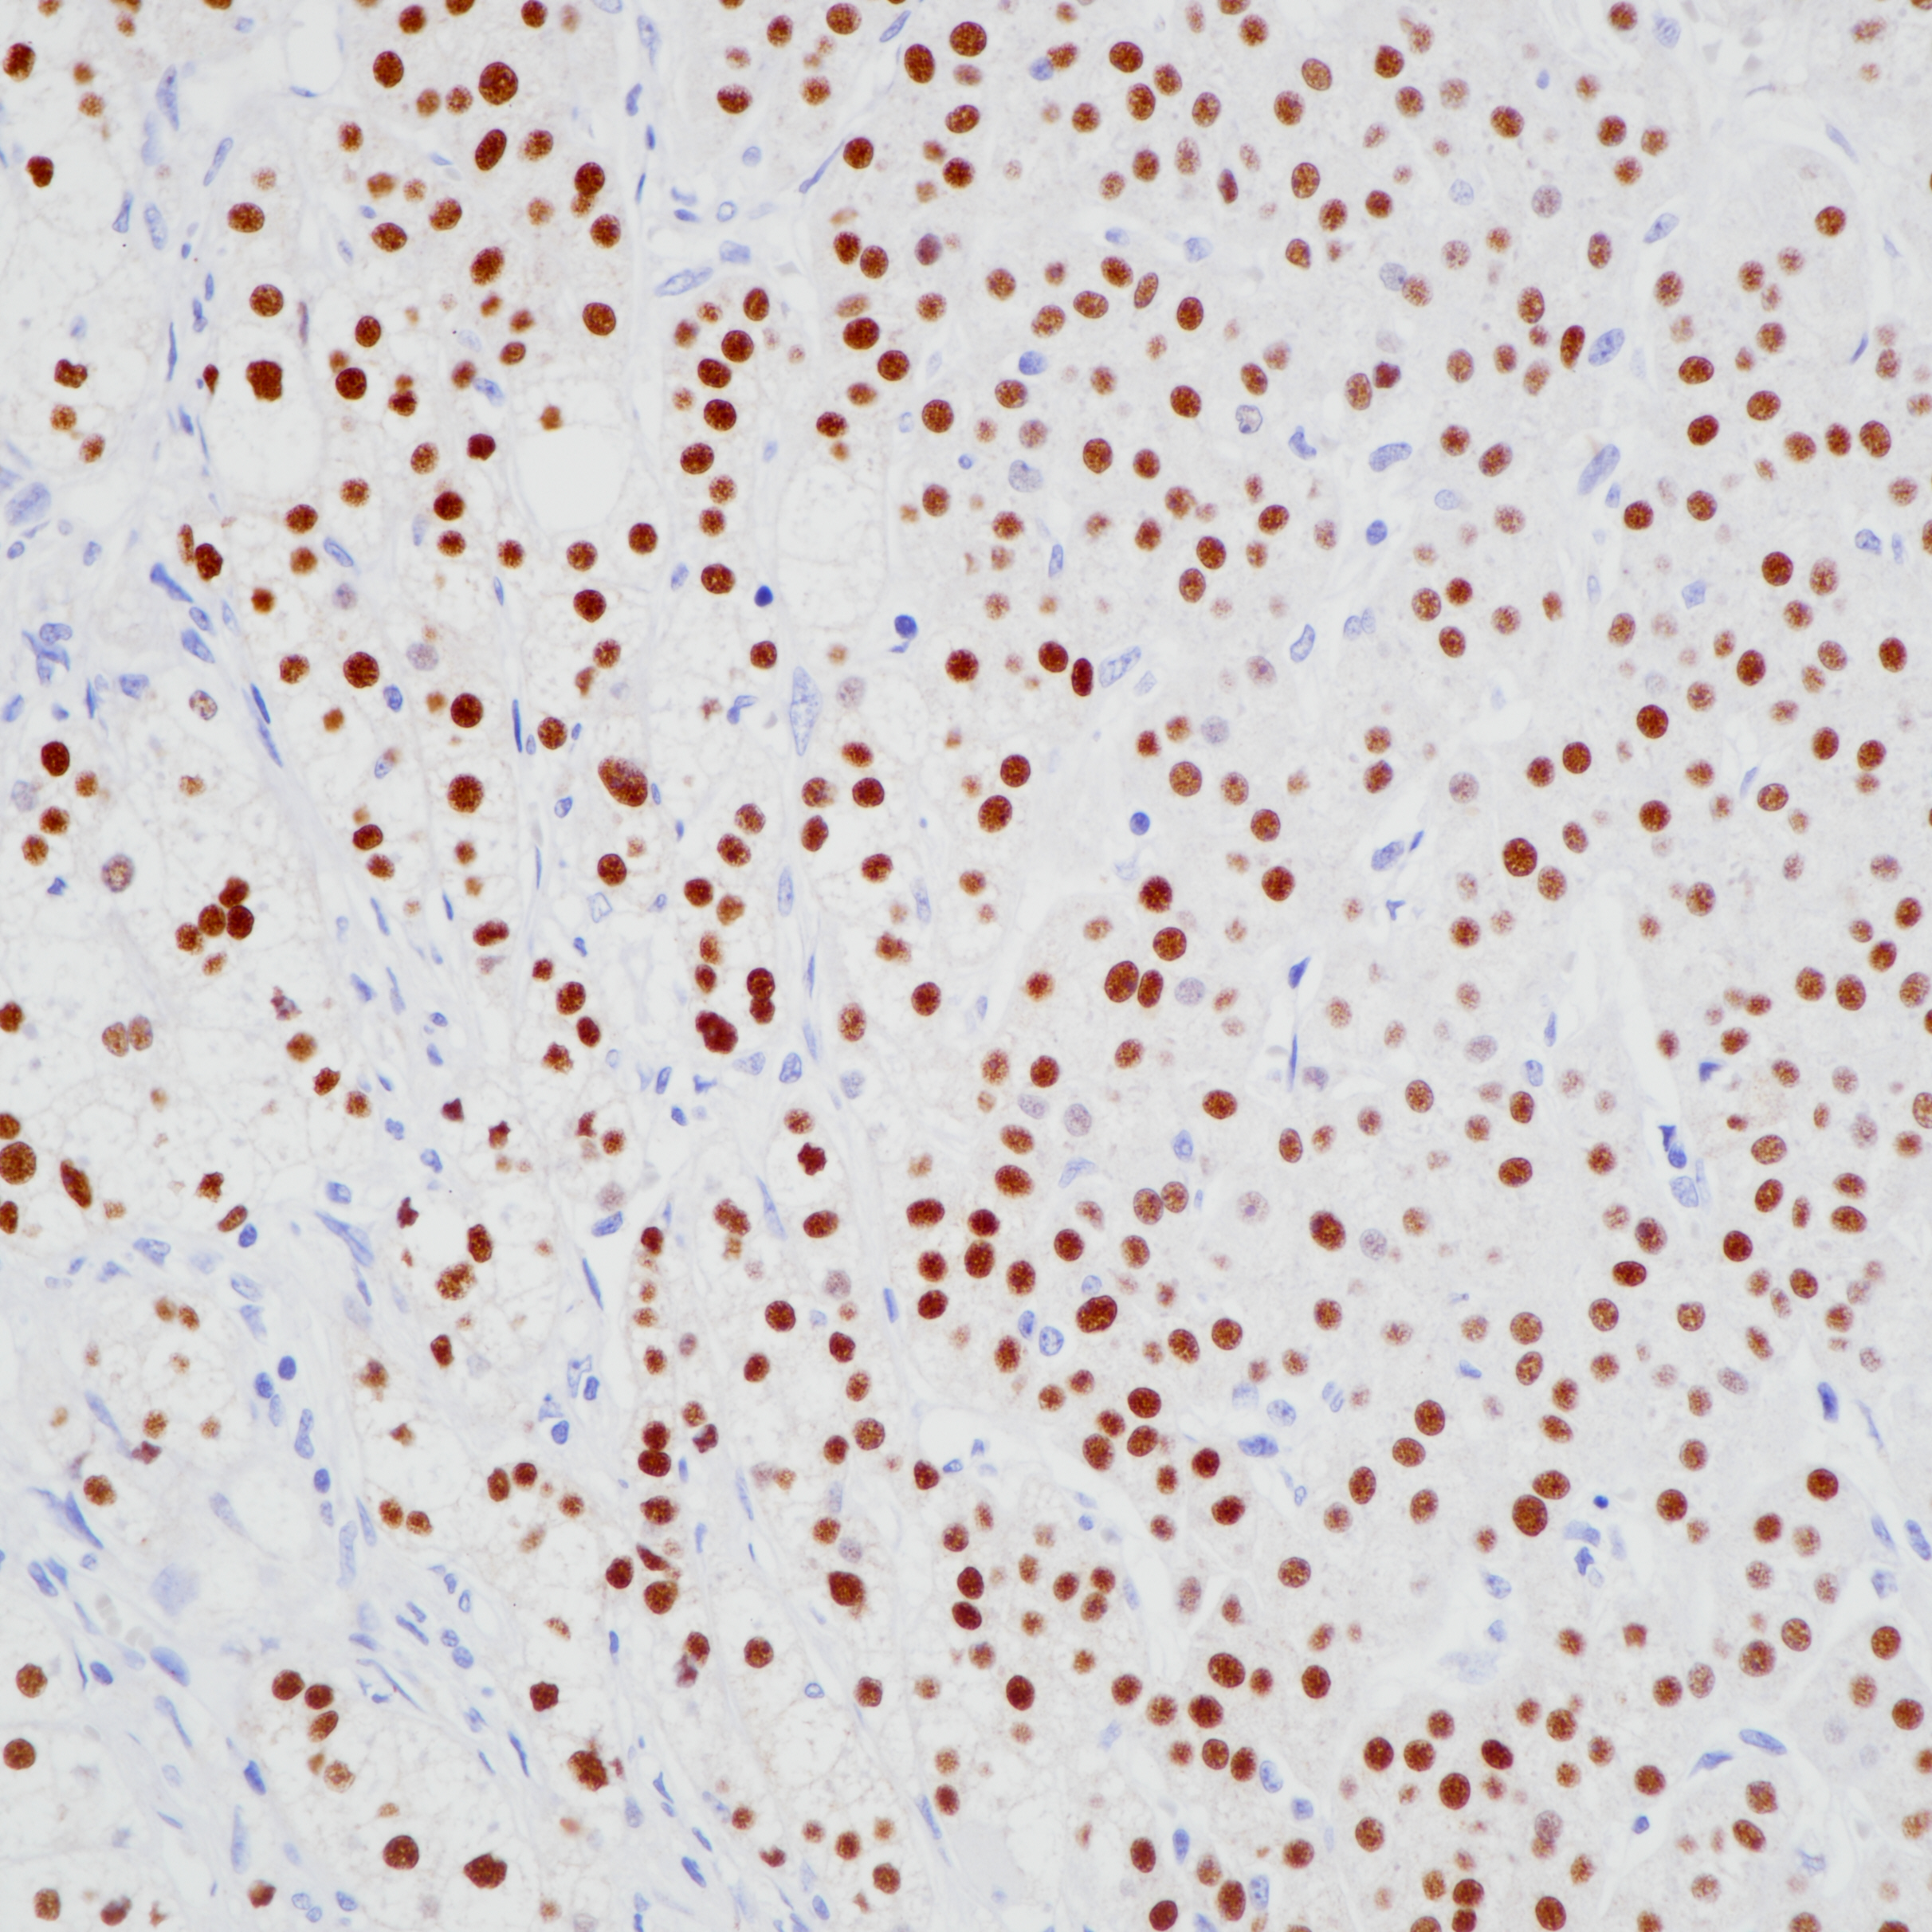

1. Gardiner JR, Shima Y, Morohashi K, Swain A. SF-1 expression during adrenal development and tumourigenesis. Mol Cell Endocrinol.2012Mar31;351(1):12-8.doi:10.1016/j.mce.2011.10.007. Epub 2011 Oct 15.

2. Młynarczuk J, Rękawiecki R. The role of the orphan receptor SF-1 in the development and function of the ovary. Reprod Biol. 2010 Nov;10(3):177-93.